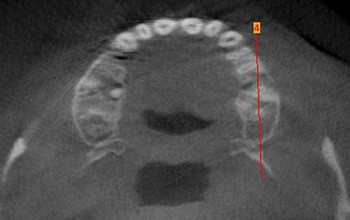

Das DVT als dreidimensionales Röntgenverfahren stellt sowohl aus zahnmedizinischer als auch aus medizinischer Sicht definitiv eine diagnostische...

Für den Einsatz der Digitalen Volumentomografie (DVT) sollte bei der Grundproblematik Parodontitis stets eine sehr genaue Indikationsstellung...